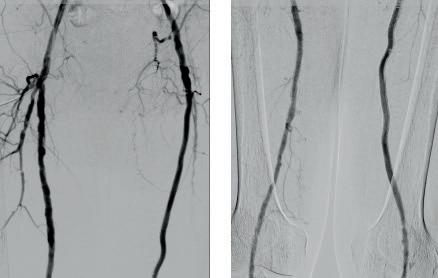

FOUR

Male, 63 years old

Operated prostate adenocarcinoma, Gleason grade 7 (3+4), PSA increase to 0.26 six years after surgery. PET PSMA (A, B) positive for right pelvic adenopathy. In the right hypogastric vein (C) we found ESR1, FGFR2 and MAP2K1 mutations. In the left (D) vein, mutations were FGFR2, MAP2K1 and RET. Pelvic radiotherapy is indicated.

Prostate adenocarcinoma (Case four) affects 16% of the male population. Early diagnosis of this cancer has

had a positive effect on survival but metastatic spread leads to a longlasting deterioration in quality of life. Peripheral sampling or selective sampling from the hypogastric veins can provide timely detection of the somatic mutations involved in resistance to radiotherapy or androgen suppression, guiding appropriate personalised treatments.